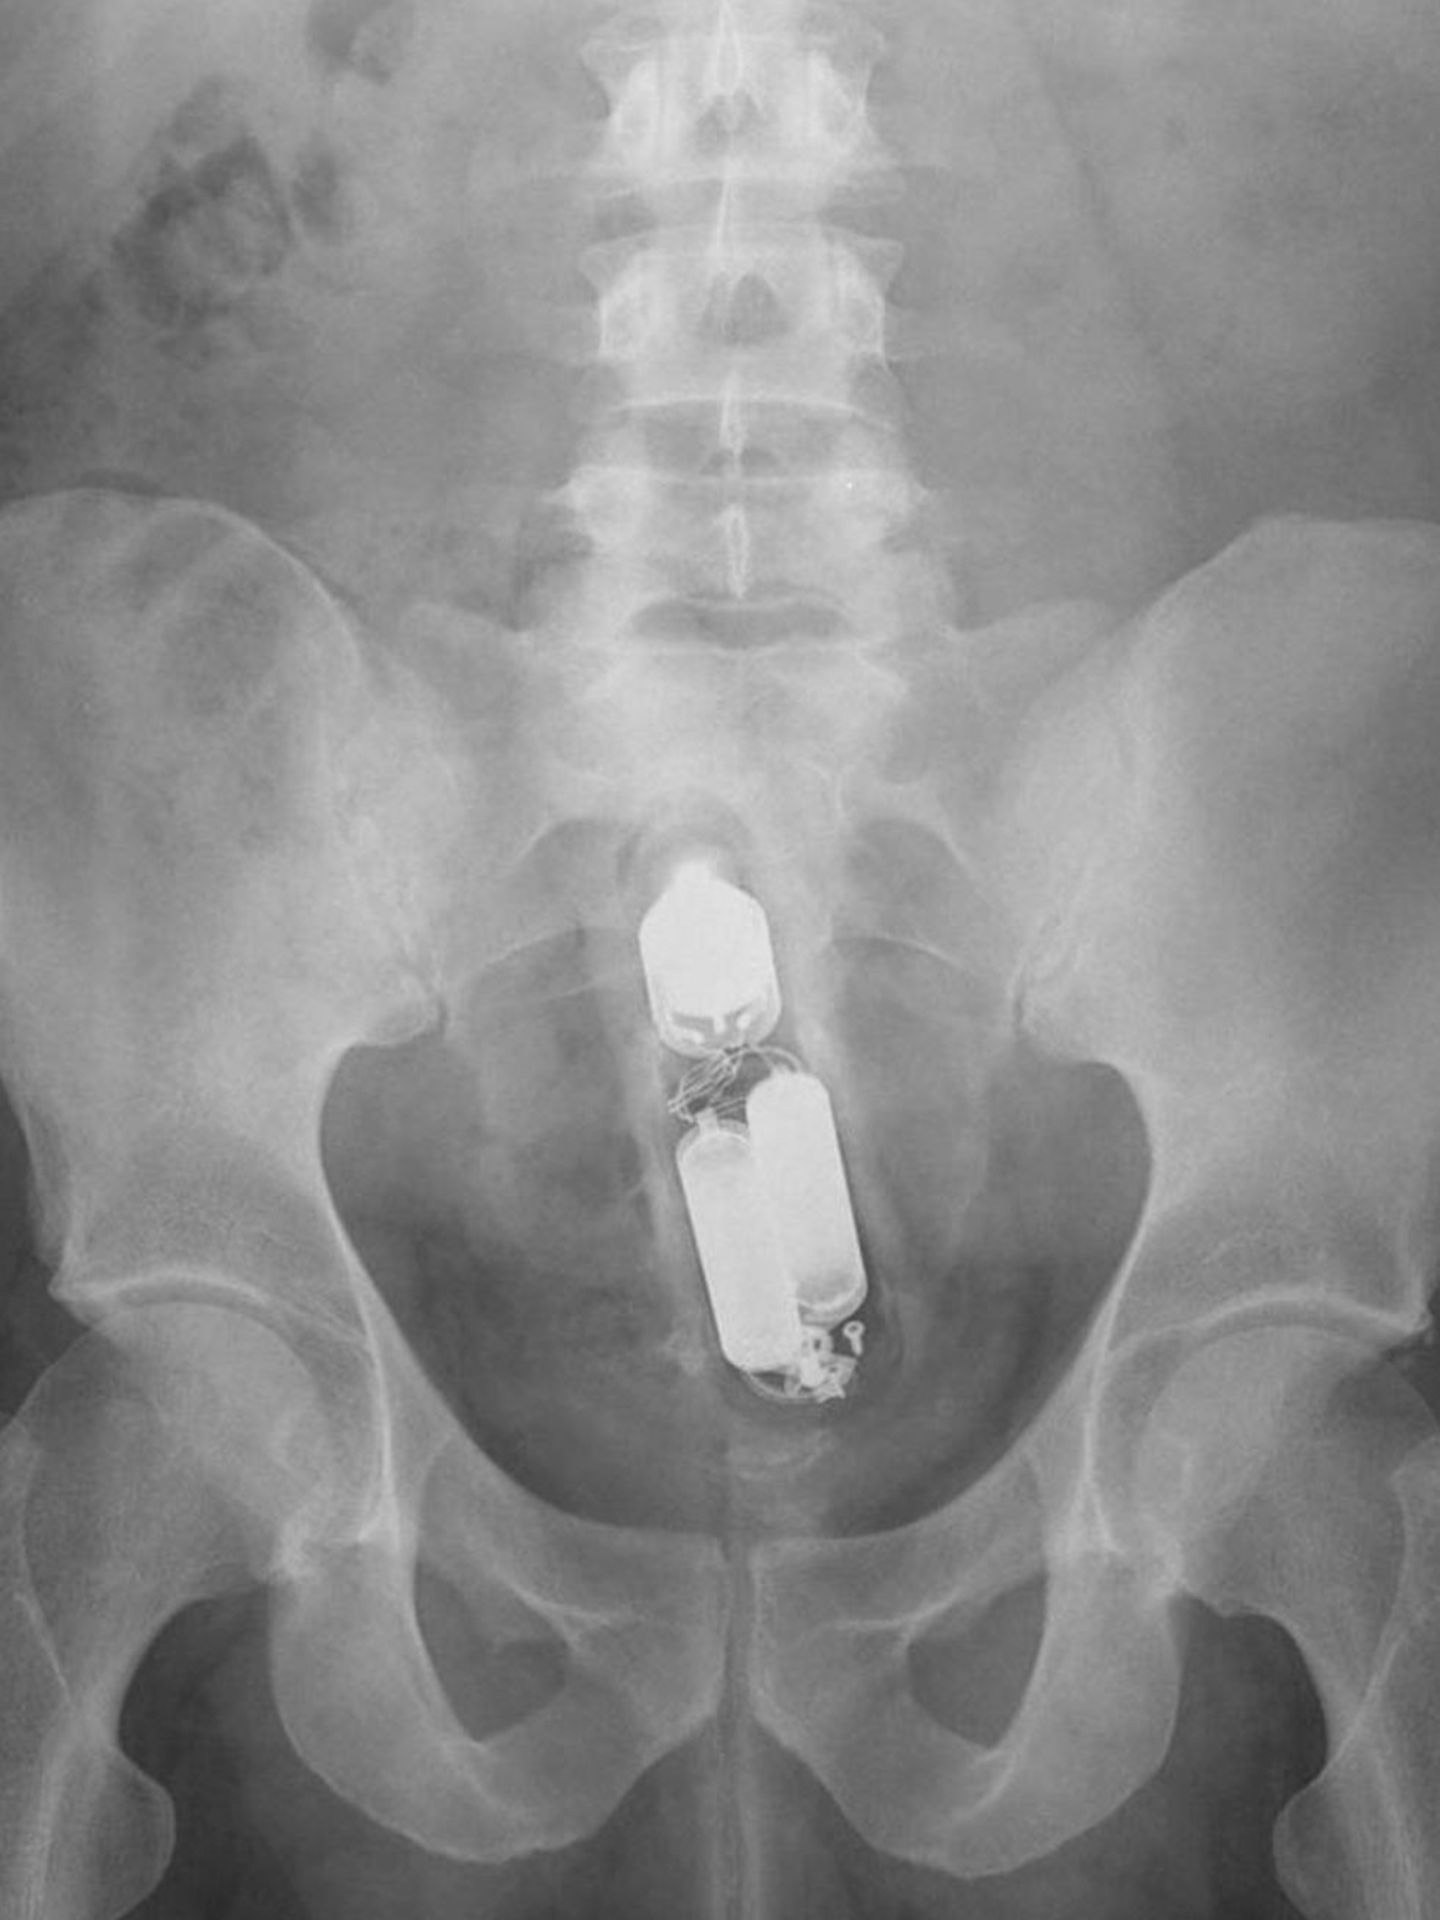

An den Batterien zu erkennen: ein Vibrator

Case courtesy of Dr Frank Gaillard, Radiopaedia.org